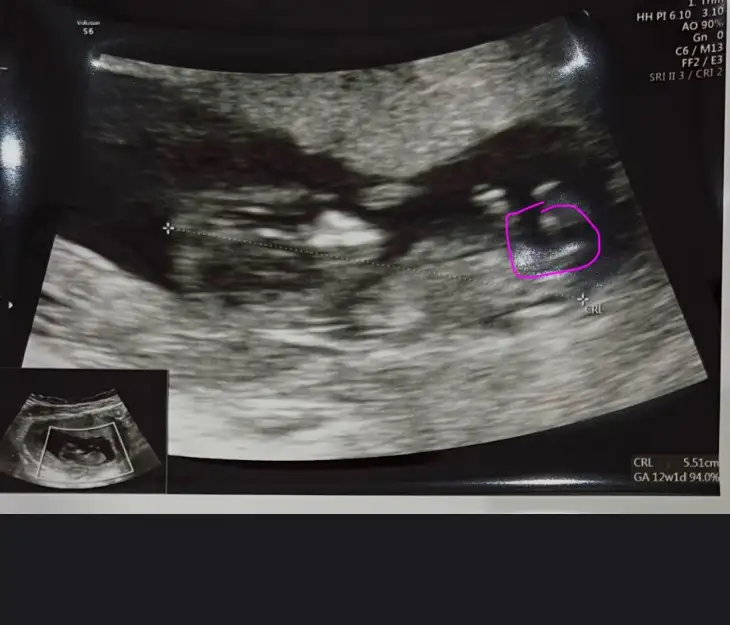

Bak işaretledimMerhaba 11+2 haftalık ultrason cinsiyet tahmini yapabilir misiniz acaba ?

Eki Görüntüle 3531429

Buda 12+2 haftalık hala aynı fikirde misiniz?Kıza benzettim ben

Buda 12+2 haftalık hala aynı fikirde misiniz acaba ?Annesi maşallah tosununayanlış görmüyorsam oğlumdaki aynı çıkıntı burada da, sağlıcakla gelsin inşallaaaah,

Evet hala erkeğe benzettimBuda 12+2 haftalık hala aynı fikirde misiniz?